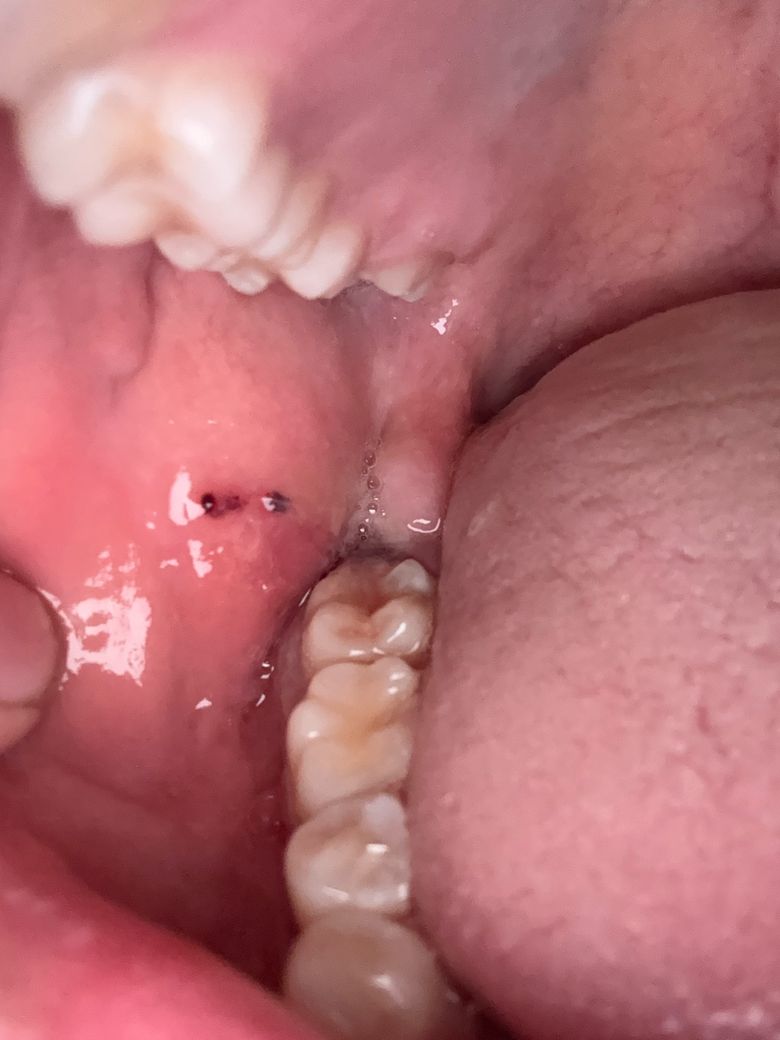

사랑니 발치후 피떡에 생긴게 뭔가요?

어제 사랑니뽑은 자리에 피떡이 생긴건 좋은데 오늘보니 그 위로 무언가 하얗게 덮어져있더라구요 이게뭔가요???

문제있나요??

• 1번 째 사진

사랑니를 발치한 이후에 회복되는 과정에서 정상적으로 생기는 것이니 너무 걱정안하셔도 됩니다.

사랑니 발치후에 잇몸이 치유되면서 생기는 자연스러운 현상이니 크게 걱정은 안하셔도 될것같습니다.

사랑니를 발치하고 나면 발치한 부위가 아물면서 가피등이 형성될수 있습니다. 이런 가피는 하얀색으로 보이는 경우도 있습니다.

문제가 되는것은 아니며 발치한 부위가 자극이 되지 않도록하는것이 좋습니다.

발치한 부위가 아무는데는 보통 2주정도의 시간이 걸리게 됩니다.

어제 사랑니뽑은 자리에 피떡이 생긴건 좋은데 오늘보니 그 위로 무언가 하얗게 덮어져있더라구요 이게뭔가요??? 치유 과정중에 생기는 부산물입니다